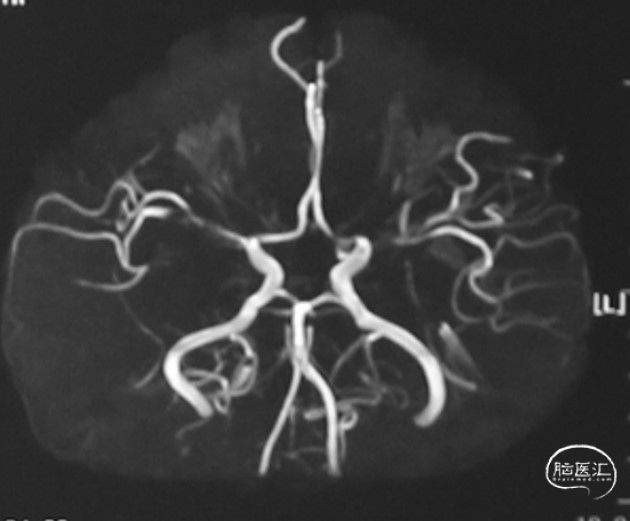

MRA:右侧大脑前动脉、大脑中动脉闭塞,左侧大脑中动脉分支减少;

左侧颈内动脉三维重建显示大脑中分支残端: